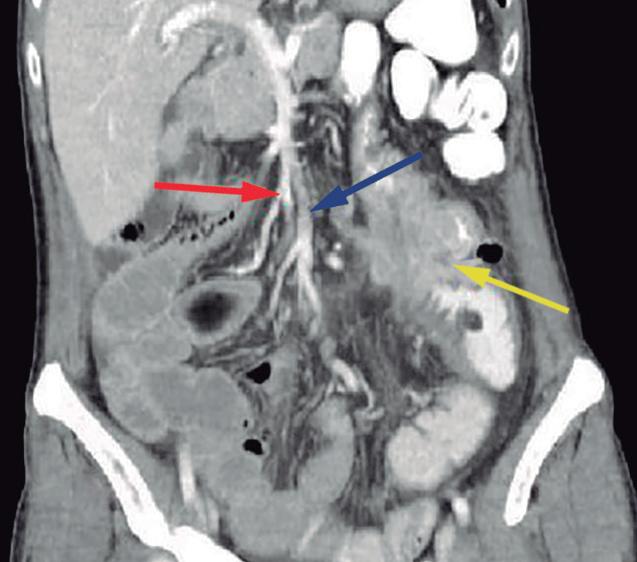

El páncreas anular en neonatos, cuando es sintomático, provoca síndrome de obstrucción gástrica, clínicamente manifestado con vómitos como consecuencia de la compresión y estenosis de la 2° porción duodenal. En los adultos también puede originar obstrucción gastrointestinal, y los pacientes presentan dolor abdominal, habitualmente postprandial y/o vómitos. En menor medida puede predisponer a PAR o bien a

Más allá del diagnóstico de esta anomalía debemos buscar signos imagenológicos indirectos de obstrucción gastrointestinal, como son la dilatación gástrica y de la 1° porción duodenal (Figura 10), con estrechez de la luz del duodeno en el sitio por donde transcurre a través del páncreas anular.18,19

A) Tomografía computada con contraste, plano coronal. El páncreas anular (flecha) provoca dilatación de la 1° porción del duodeno (cabezas de flecha). B) Tomografía computada con contraste, plano axial. Flechas: páncreas anular. Cabeza de flecha: duodeno. C) Tomografía computada con contraste, plano axial, corte más caudal que el previo. Flechas: páncreas anular.